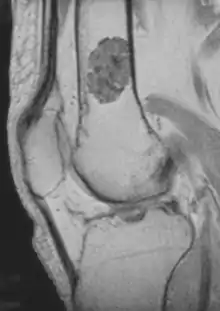

الورم الغضروفي الباطن (بالإنجليزية:Enchondroma) عبارة عن كيسة غضروفية في نخاع العظام تُكتشف أثناء التصوير بالأشعة السينية ولديها مظهر مميز أتناء التصوير بالرنين المغناطيسي

- التصوير باستخدام الرنين المغناطيسي[1]